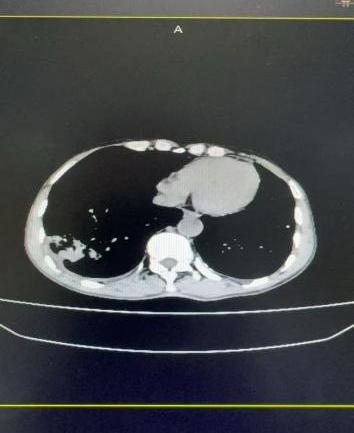

案例一:谭先生,66岁,右肺鳞癌IIIA期。2025年11月18日,在DSA引导及局麻下行经导管支气管动脉栓塞化疗术,术后肿瘤血供明显减少。

栓塞前血供丰富                                                 栓塞后血供明显减少